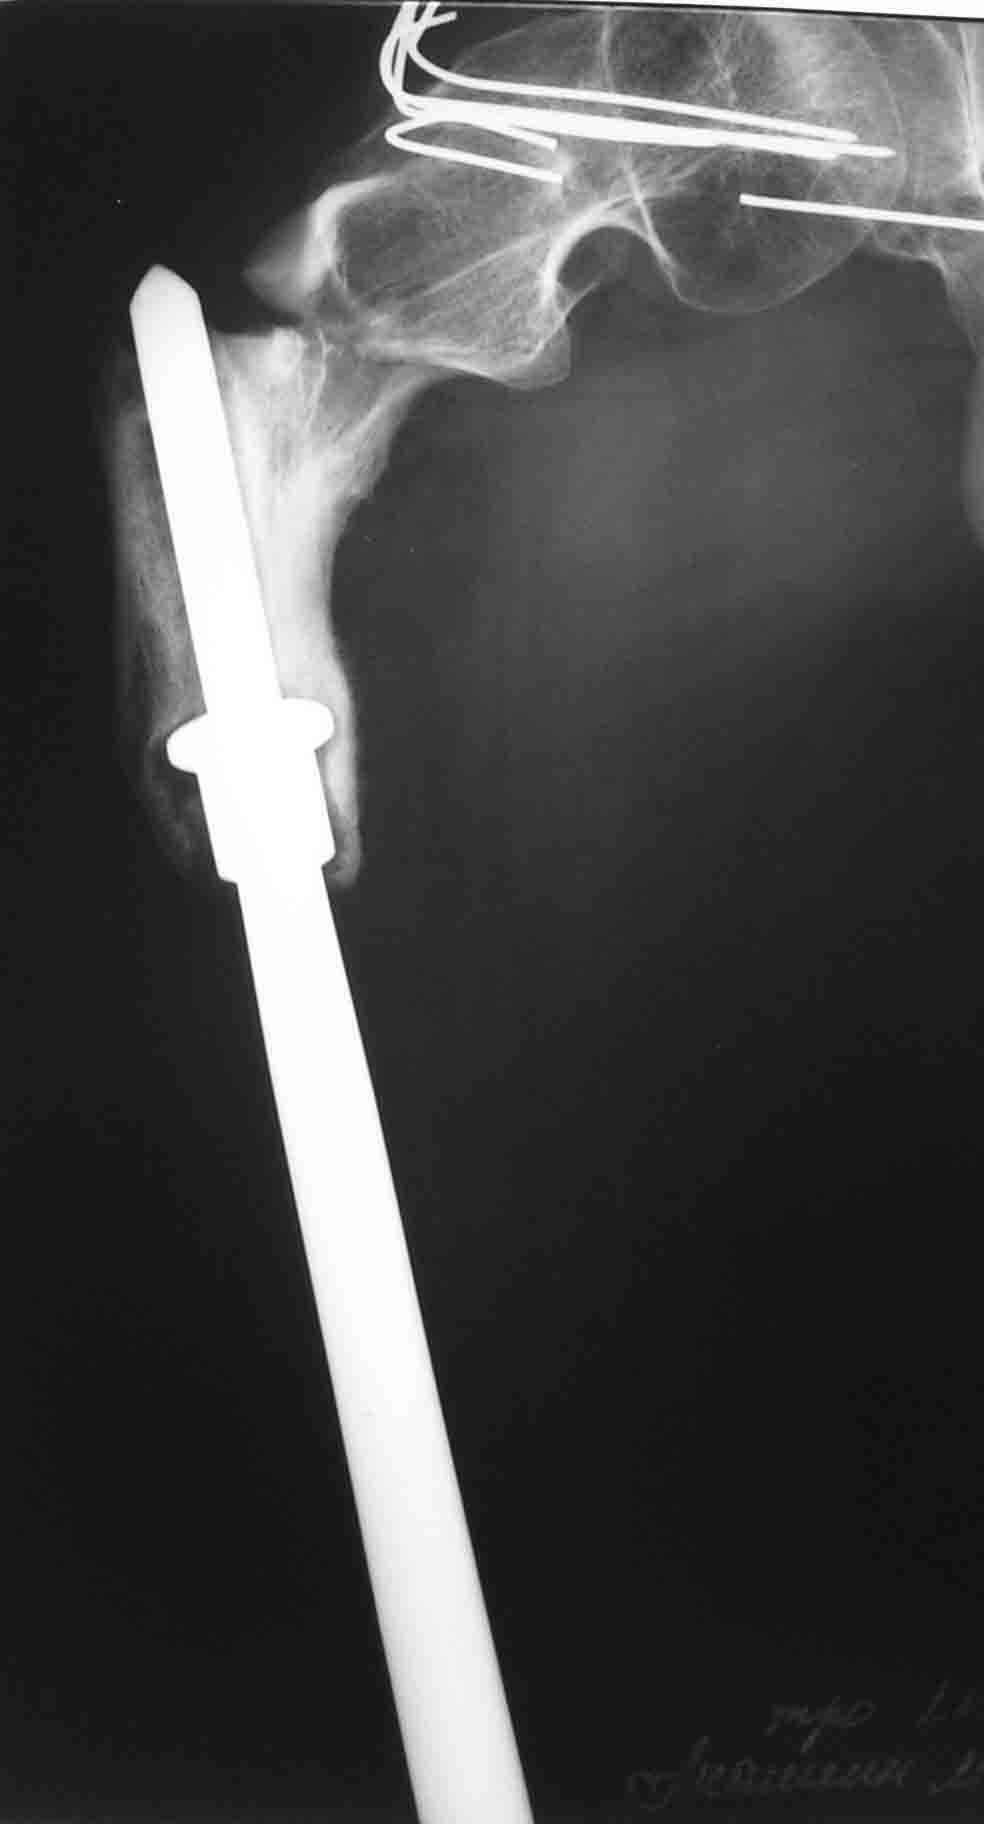

В 1998 году - перелом шейки бедра- оперирован в детской больнице (остеосинтез пучком спиц). В 2001 году- подвертельный перелом (полгода в коксите- сращение). В марте этого года- повторный подвертельный перелом (см RG). В настоящее время в коксите. Что дальше? Облздрав выделяет на лечение чуть более 100 тыс руб. (квота) Может кто-нибудь помочь пациенту? С уважением Ганин Алексей.

March 2004 - a new fracture at the place, images attached. Now the patient is in the cast again.

"subtotal resection of the femur for osteosarcoma" How much femur was removed or left? It's hard to tell from the radiographs.

A cable plate could provide stabilization of the remaining fractured proximal femur. Fixed angle device proximally (blade, screw or locking plate) with distal fixation of the plate to the bone/bone replacement prosthesis by means of cables. If there is bone in the subtrochanteric region (hard to see on the radiographs) then unicortical screws might also be possible. Of course, remove the wires in the femoral neck and head.

I'll request more informative views. But at the presented view of the

proximal femur the bone end can be seen - just below the "collar".

Yes, it is a long stem onco implant.

Создается впечатление, что причиной повторного подвертельного перелома бедра является нестабильность протеза( сложно судить о тибиальном компоненте по Рг грамме, но видимая часть бедра - на всем протяжении зона остеосклероза с истончением кортикала) Нестабильное *железо* вызывает резорбцию кости, ее ослабление и как результат -перелом ( обычно на уровне верхушки ножки протеза - зона стресса).

Согласен с Александром, что для фиксации такого перелома невозможно найти стандартное решение. Идея интрамедуллярной фиксации заманчива, но технически трудновыполнима (опил и сверление стержня протеза+ нарезка резьбы.....) и сомнения в плане окончательной стабильности фиксации, коль скоро сам бедренный компонент нестабилен.